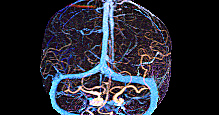

DeepClue-Precise CT 측부혈류영상

Perfusion CT를 이용한 측부혈류영상

동맥기

모세혈관기

조기정맥기

후기정맥기

지연기

MRA collateral map: ‘DeepClue-Precise MR 측부혈류영상'

MR 혈관영상을 이용한 측부혈류영상

Perfusion MRI를 이용한 측부혈류영상

측부혈류영상과 동시 생성하는

동맥영상(Arteriography), 정맥영상(Venography), 역동적 혈관영상(Dynamic Angiography)

추가 촬영없이 측부혈류영상과 동시에 생성하는 세계최초 딥클루의 원천 기술

Simultaneous Vascular imaging

3D 동정맥영상

3D 동맥영상

3D 정맥영상

4D 혈관영상